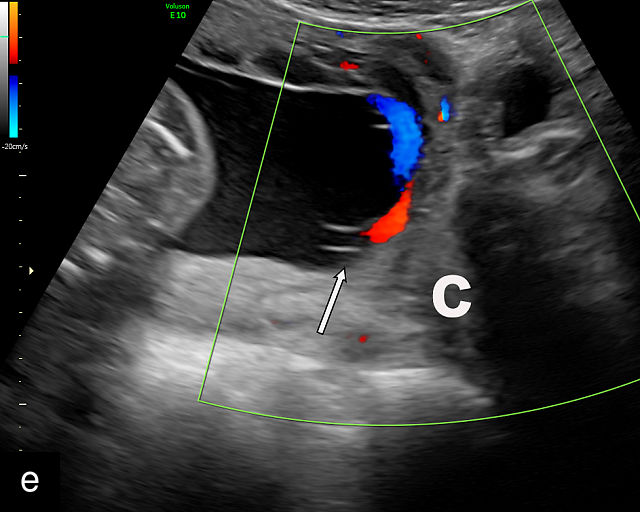

21

(a) Type-1 vasa previa. Photograph after delivery showing the umbilical cord inserting into the membranes through which unprotected fetal vessels run to insert into the placental edge. (b) Type-2 vasa previa. Photograph after delivery showing bilobed placenta with unprotected fetal vessels running though the membranes between the lobes. (c) Type-3 vasa previa in a twin pregnancy. Photograph after delivery showing unprotected vessels running through the membranes from one edge of the placenta to another (arrow). (d) Transabdominal grayscale ultrasound of the lower uterine segment showing a linear hypoechoic structure (fetal vessel) running over the cervix (c) indicating vasa previa (Type 2). b, bladder; h, fetal head. (e) Transabdominal color Doppler ultrasound of the lower uterine segment showing fetal vessels (arrow) running over the cervix (c) indicating vasa previa (Type 2). (f) Transabdominal ultrasound with color flow and pulsed-wave Doppler of the lower uterine segment showing a fetal vessel running over the cervix (c) indicating vasa previa (Type 2). Pulsed-wave Doppler demonstrates an umbilical arterial waveform. (g) Transvaginal grayscale ultrasound with showing a Type-2 vasa previa. There are two placental lobes, an anterior (a) and a posterior (p) lobe. There is a linear and circular hypoechoic structure (arrow) running over the cervix (c) between the lobes. (h) Transvaginal grayscale ultrasound image of vasa previa. A hypoechoic linear structure (arrow) is seen running through the membranes over the cervix (c). h, fetal head. (i) Transvaginal grayscale ultrasound of vasa previa. Hypoechoic circular and linear structures are seen close to the internal os. (j) Transvaginal color Doppler ultrasound image of vasa previa. A fetal vessel is seen running through the membranes over the internal os (arrow) of the cervix (c). h, fetal head. (k) Transvaginal ultrasound with color Doppler showing a Type-2 vasa previa. There are two placental lobes, an anterior and posterior lobe (pl). Fetal vessels run over the cervix between the lobes. (l) Transvaginal color flow ultrasound with pulsed-wave Doppler image of vasa previa. Color Doppler shows flow through the vessel and pulsed-wave Doppler shows a fetal umbilical venous waveform. (m) Transvaginal color ultrasound with pulsed-wave Doppler image of vasa previa. Color flow Doppler shows flow through the vessel and pulsed-wave Doppler shows a fetal umbilical arterial waveform. (n) Transvaginal three-dimensional ultrasound with color Doppler image of vasa previa. h, fetal head; c, cervix.

12

Transvaginal ultrasound imaging of Type-1 vasa previa. Color Doppler (a,c,d) and grayscale (b) imaging shows fetal vessels running over the cervix.

In all pregnancies, the placental cord insertion should be identified at the time of the second-trimester anatomy scan. In addition, a color flow Doppler sweep of the region overlying the cervix should be performed. The ultrasound appearance of vasa previa is of hypoechoic linear or circular structures overlying or in close proximity to the internal os (Figure 21).30,187,252,263 When these are observed, color flow Doppler should be employed to confirm flow through these structures.30,187 Transvaginal ultrasound with color and pulsed-wave Doppler is essential for diagnosing vasa previa; the presence of a fetal arterial or venous waveform on pulsed-wave Doppler confirms the diagnosis (Figure 21). A common misconception is that vasa previa occurs only when a fetal artery overlies the cervix; however, a fetal vein overlying the cervix also constitutes vasa previa (Figure 21l).265 The precise distance of fetal vessels from the internal os required to define vasa previa has been debated.266 While some have used a distance of 2 cm, others argue that unprotected fetal vessels within 5 cm of the internal os are at risk of rupture, particularly given that the cervix dilates to 10 cm during labor. Some experts advocate for a 5-cm threshold to define vasa previa.266,267 An international Delphi consensus of vasa previa experts recommended that the definition should not be limited to a 2 cm cutoff, acknowledging the variability in clinical practice.268

Transvaginal ultrasound with color flow Doppler is highly accurate in the diagnosis of vasa previa, with a systematic review and meta-analysis finding sensitivity and specificity of greater than 99%.269

False positives may arise due to several factors, including funic presentation (where free loops of the cord overlie the cervix), movement artifacts on color Doppler, placenta previa or maternal vessels.30,263 Free loops of the umbilical cord typically move away from the cervix with changes in maternal position and do not persist on serial ultrasound examinations.187

When vasa previa is suspected during the second trimester, transvaginal sonography with color Doppler should be repeated at around 32 weeks to confirm the diagnosis. This follow-up is essential, as 15–40% of vasa previa cases identified in the second trimester resolve spontaneously before delivery.270,271 It is also critical to ensure that the fetal head is not engaged, as this can compress and obscure fetal vessels, potentially leading to a false-negative diagnosis.272 In such cases, manual elevation of the fetal head may be necessary, but care must be taken to avoid compressing the vessels during this maneuver, as it can also result in a missed diagnosis.273